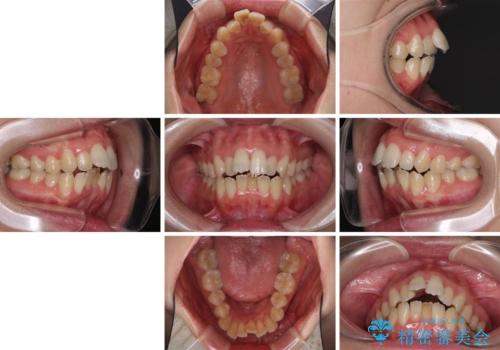

Eラインを改善したい ハーフリンガルによる抜歯矯正

- 口元の突出感を気にして来院された患者様です。

上下左右の第一小臼歯4本を抜歯して口元を下げる治療計画としました。

舌の突出癖が強く、口元を引っ込める力に拮抗してしまい、抜歯スペースを閉じるまでに時間がかかりました。

また途中出産もありましたが、無事に治療を終えることができました。